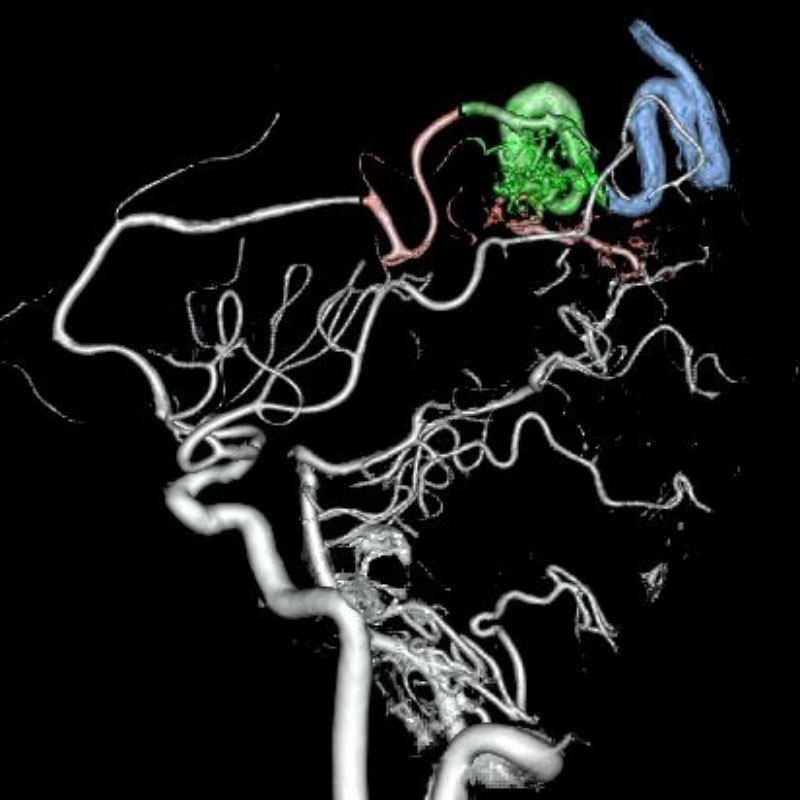

脳動静脈奇形

血管塞栓術

松田/濵田/元永